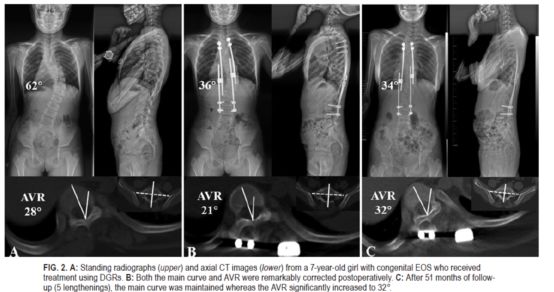

本研究探讨早发型脊柱侧凸(EOS)患者传统双生长棒(DGRs)轴位旋转矫正效果,进一步探讨轴位和躯干畸形的关系。

作者回顾性分析2006年1月至2014年12月间应用传统DGRs治疗EOS患者的临床资料。X线平片评估冠状位和矢状位畸形的程度。在顶椎层面CT扫描上测量顶椎旋转(AVR)和肋骨驼峰样隆起(RH)。用Pearson 或Spearman相关分析方法来分析脊柱和躯干畸形之间的关系。作者共纳入27例患者(男10例,女17例,平均年龄6.5±1.7岁)。每例患者的延长数为5±1.9,平均随访时间为52.9±18.2个月。顶椎偏移、顶椎椎体肋骨比(AVB-R)、AVR和RH参数在初次手术后显著降低(p<0.05),但在最近的随访评估中显示出显著进展(p<0.05)。AVR术前值及术后矫正值与Cobb角、AVB-R、RH的矫正值显著相关。从最初的手术到最近的随访期间,AVR与AVB-R的恶化,以及AVR与RH的恶化之间均发现显著的相关性。

作者据此给出结论,DGRs技术在初次手术后可明显改善AVR矫正情况,但该技术在随访中很难防止AVR的恶化。

![]()